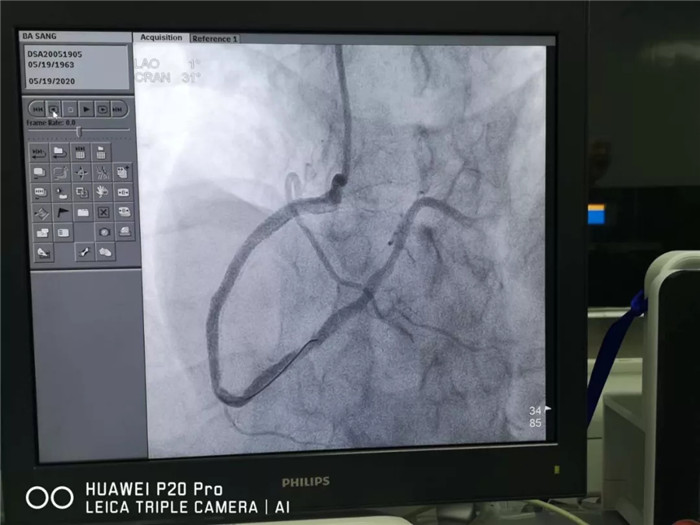

西藏阜康醫(yī)院內(nèi)三(心內(nèi))科值班醫(yī)生迅速查體檢查,診斷“冠心病-急性心肌梗死(下壁)”。急行冠狀動脈造影檢查結(jié)果顯示:心臟冠狀動脈急性閉塞病變。

640.webp.jpg

術(shù)前影像